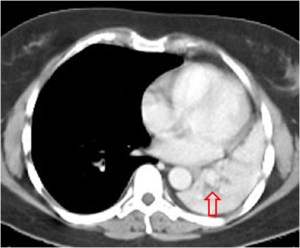

SIGNO DEL CASQUETE APICAL IZQUIERDO

La aparición de una densidad en el ápex pulmonar izquierdo, de borde inferior cóncavo y bien delimitado (casquete apical) en un paciente con traumatismo torácico, debe hacernos sospechar la existencia de una rotura aórtica.

Deben excluirse otras causas de casquete apical, especialmente las lesiones residuales tuberculosas, que suelen acompañarse de otros hallazgos como tractos fibrosos pleuro-parenquimatosos, pérdida de volumen en el lóbulo superior, granulomas, etc.

Mostramos un caso de rotura aórtica por accidente de moto. En este paciente también aparece el signo de la alteración del contorno aórtico.

En el corte de TC de tórax con contraste intravenoso del mismo paciente vemos la rotura aórtica (flecha verde), un hemotórax bilateral –algo más cuantioso en el hemitórax izquierdo- (flechas azules) y un hematoma mediastínico (flecha naranja).